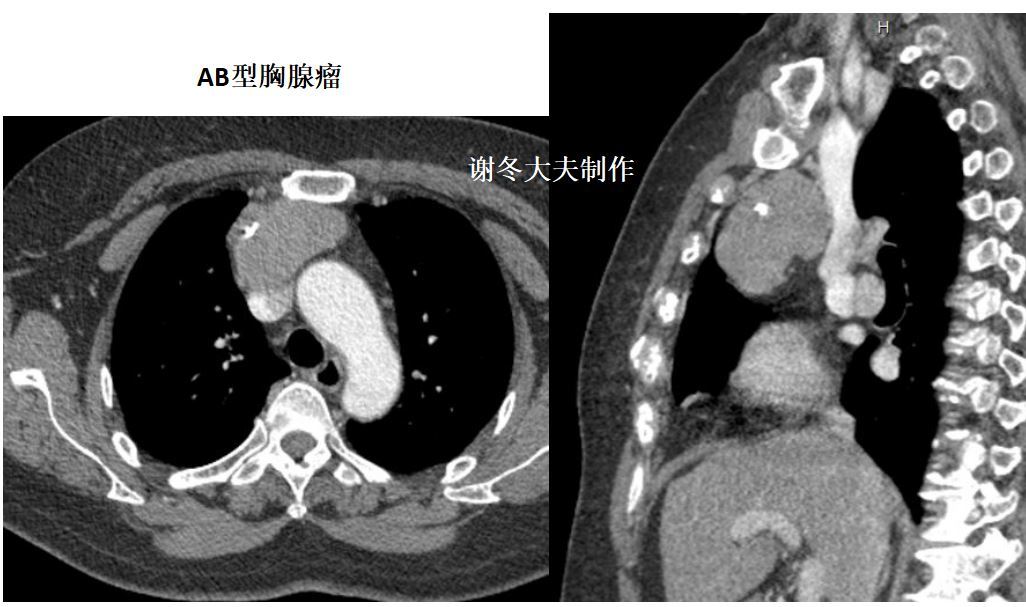

我的66例胸腺瘤,大多数是偏侧生长的, 大小也常常为大家所忽略

大部分肿瘤生长不对称,居于前纵隔的一侧; 直径 2cm的胸腺瘤可仅表现